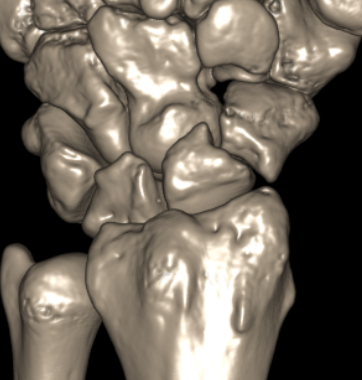

CT

Indication

- diagnose nonuion

- identify humpback deformity

- plan size and shape of bone graft

Failure of fracture to unite at 3 months on CT scan

Nonunion with flexion deformity